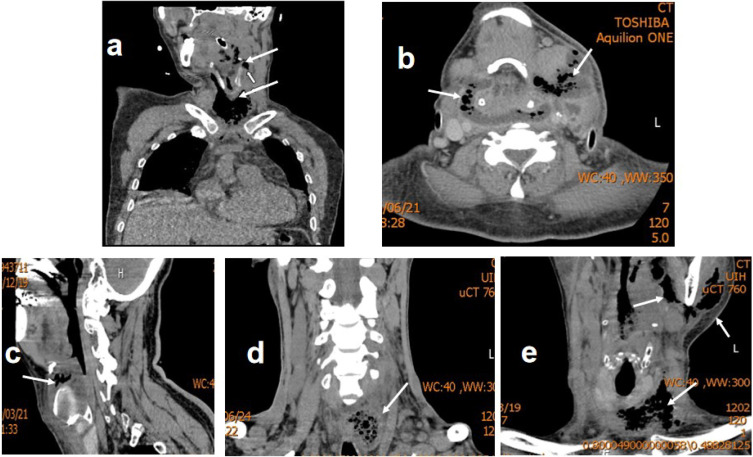

Results: All five patients were diagnosed via neck CT and surgical exploration. Bacterial cultures predominantly revealed mixed infections of Klebsiella and other gram-negative bacilli, along with anaerobic bacteria. Three patients had diabetes, two presented with diabetic ketoacidosis, and three had mediastinal involvement. Three patients underwent tracheotomy, while two required tracheal intubation. All patients were treated with neck incision, drainage, regular dressing changes, and targeted antibiotic therapy. They had an average hospital stay of 35.8 days, and all were discharged fully recovered.

Conclusion: Severe DNSI tends to occur in patients with diabetes and other underlying systemic conditions. Infections involving multiple deep neck spaces, such as the parapharyngeal, pretracheal, and prevertebral spaces, leading to high-risk complications like airway obstruction, cervical necrotizing fasciitis, mediastinitis, and sepsis, are considered severe DNSI. Early diagnosis, timely surgical exploration, drainage to maintain airway patency, and targeted antibiotic therapy are crucial to effective management.